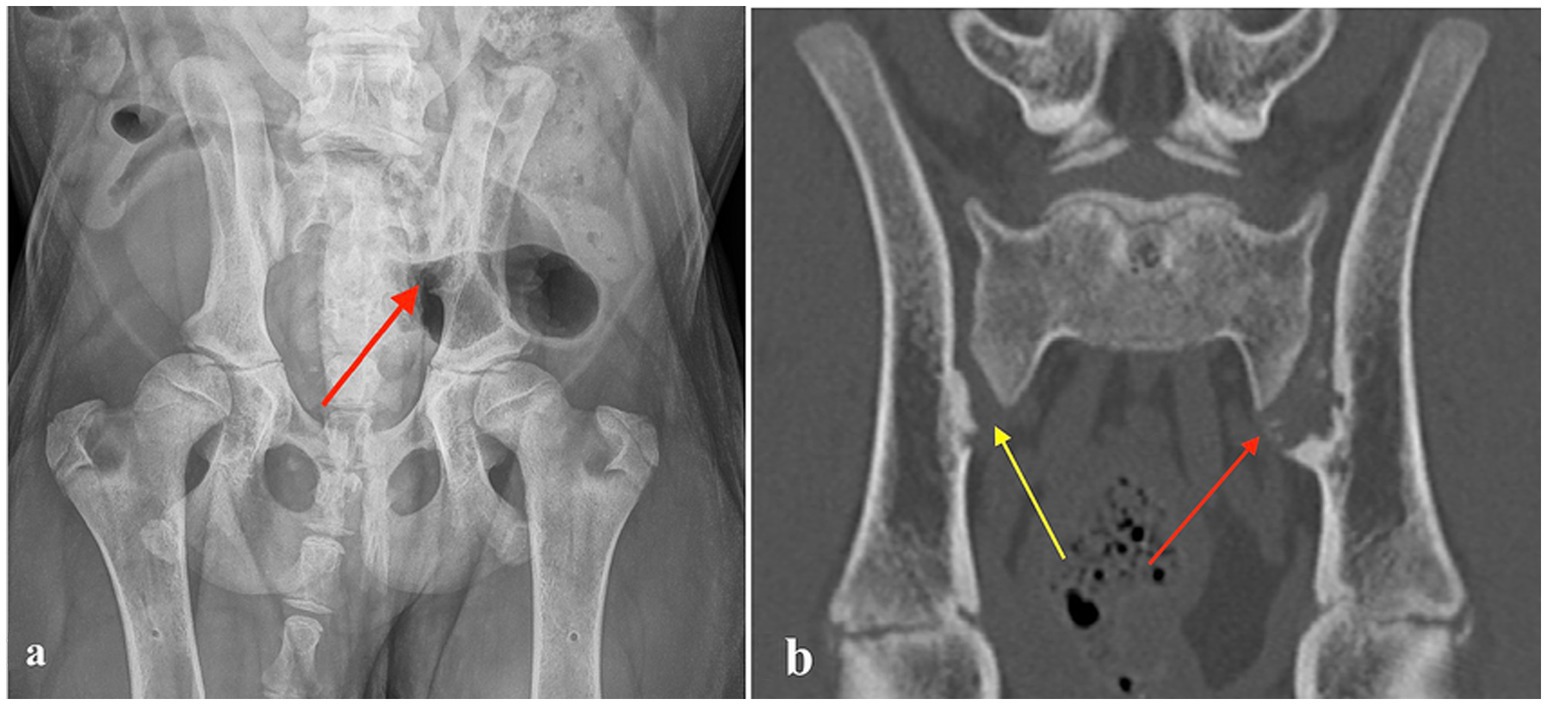

A four-month-old intact male Bernese Mountain Dog, weighing 20.8 kg, was presented for an orthopedic examination due to an abnormal hind limb gait and gradually worsening hyperextension of the right tarsus for the last 2 weeks. The dog had always been unwilling to jump onto the couch but otherwise moved normally. It was clinically healthy with no previous infections or predisposing illnesses. On orthopedic examination, palpation of the lumbosacral region elicited pain. The gait of the hind limbs was mildly stiff and a bit wide with some abduction. Moderate right tarsal hyperextension and mild left tarsal hyperextension, as well as mild metatarsal outward rotation, were also observed. The remainder of the orthopedic examination was unremarkable. The dog was sedated, and radiographs of the lumbar vertebrae and pelvis were obtained. The radiographs revealed erosive SIJ lesions on the left side and mild hip laxity (Figure 1). CT imaging was performed to obtain more precise information regarding the SIJ lesions. The CT study revealed multiple small, randomly distributed cystoid and irregularly shaped concave defects within the joint surfaces of both SIJs, with deep peripheral sclerosis (Figure 2b). Asymmetric widening of the SIJ spaces was also observed. The changes were severe on the left side and moderate on the right side. Both the radiographic and CT examinations also revealed changes in the coxofemoral joints consistent with mild canine hip dysplasia. The presumptive diagnosis for the clinical signs was inflammatory and infectious sacroiliitis. Degenerative and neoplastic diseases were considered less likely due to the patient’s age, clinical signs, and CT findings.

Figure 1. (a) Ventrodorsal radiograph of a four-month-old Bernese Mountain Dog with erosive lesions in the left sacroiliac joint (red arrow). (b) Computed tomography image (coronal plane) of the same dog, showing multiple small, randomly distributed cystoid and irregularly shaped concave defects within the left sacroiliac joint surface with deep peripheral sclerosis (left side red arrow). Similar but milder defects are visible on the right side (yellow arrow).